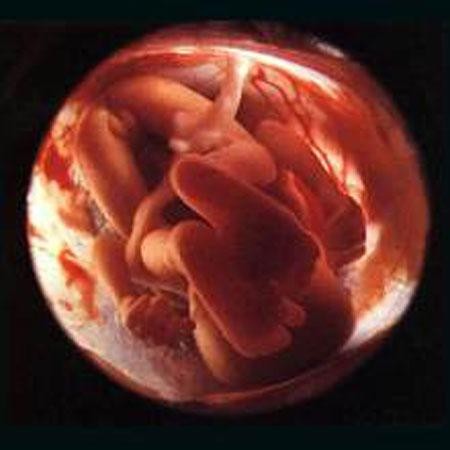

16-17 недель беременности: развитие малыша